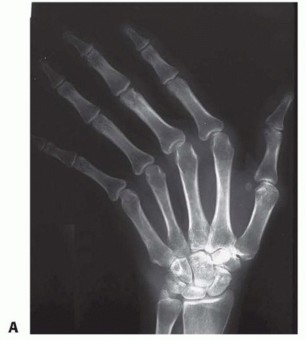

Radiographic evaluation is the ultimate arbiter of surgical candidacy. High-quality, multi-planar radiographs must demonstrate Larsen Grade 1 or 2 changes—specifically, periarticular osteopenia and marginal erosions, but with preservation of the joint space and an absence of significant architectural destruction or fixed volar subluxation. If the joint space is obliterated or if there is severe, uncorrectable volar subluxation with bone-on-bone articulation, soft tissue realignment will inevitably fail. In such advanced cases (Larsen Grades 3-5), the surgeon must pivot to joint arthroplasty (e.g., silicone interpositional arthroplasty) or arthrodesis.

Figure 3: Preoperative radiograph demonstrating classic extensor tendon subluxation and ulnar deviation of the MCP joints, notably with well-maintained joint spaces, making this an ideal candidate for soft tissue reconstruction.

Figure 4: Radiograph depicting extensor tendon subluxation and ulnar deviation with reducible MCP joint subluxation of the index and middle fingers. The lack of severe erosive changes is the key indicator for synovectomy and centralization over arthroplasty.

Clinical & Radiographic Imaging Archive